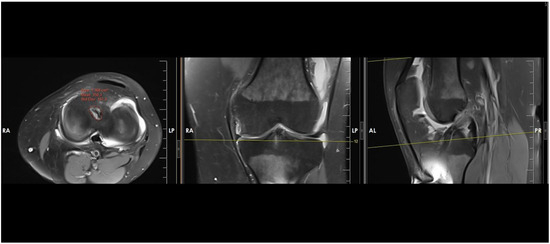

Influence of Intra-Articular Tunnel Aperture Morphology on Clinical Outcomes and Graft Rerupture After ACL Reconstruction

Background/Objectives: Variations in drill orientation during femoral and tibial tunnel creation can alter intra-articular tunnel aperture morphology in anterior cruciate ligament (ACL) reconstruction. Enlarged or irregular apertures may affect graft–tunnel conformity and graft mechanics. This study aimed to assess the relationship between intra-articular [...] Read more.

Background/Objectives: Variations in drill orientation during femoral and tibial tunnel creation can alter intra-articular tunnel aperture morphology in anterior cruciate ligament (ACL) reconstruction. Enlarged or irregular apertures may affect graft–tunnel conformity and graft mechanics. This study aimed to assess the relationship between intra-articular femoral and tibial tunnel aperture areas, postoperative clinical outcomes, and graft rerupture. This study specifically focuses on MRI-based measurement of intra-articular tunnel aperture area, a morphological parameter that has not been routinely evaluated in previous ACL reconstruction studies and differs conceptually from tunnel diameter or drilling angles. Methods: This retrospective case–control study included patients who underwent primary ACL reconstruction with an 8 mm hamstring autograft using the anteromedial portal technique. All patients completed a minimum 2-year follow-up and postoperative MRI. Femoral and tibial intra-articular aperture areas were measured on MRI Clinical outcomes (Lysholm scores and KOOSs) in patients with intact grafts. Patients were categorized into intact-graft and rerupture groups. Correlation analyses were used to evaluate associations between aperture areas and clinical outcomes. Logistic regression identified predictors of rerupture. Results: A total of 152 patients met the inclusion criteria, including 13 with graft rerupture. In the intact-graft group, mean femoral and tibial aperture areas were 127.34 ± 8.92 mm2 and 138.33 ± 7.08 mm2, respectively. Both aperture areas demonstrated significant negative correlations with Lysholm scores and KOOSs. Patients with rerupture had significantly larger femoral (145.26 ± 4.22 mm2) and tibial (158.02 ± 2.88 mm2) aperture areas (p < 0.001 for both). Logistic regression identified tibial aperture area as a significant predictor of rerupture. Conclusions: Larger intra-articular tunnel aperture areas were associated with inferior functional outcomes, and increased tibial aperture area correlated significantly with graft rerupture. Aperture morphology may represent an important factor influencing graft integrity and postoperative recovery after ACL reconstruction. Full article